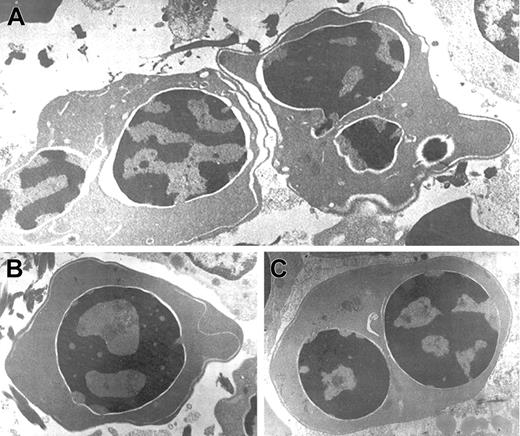

Electron microscopic aberrations were more prominent in late erythroblasts (Figure 2). The nuclear outline was often undulated or lobulated, and the nuclear membrane–associated heterochromatin was frequently absent over large areas of the nuclear membrane. In some cells, the heterochromatin was spongy and showed numerous “punched out” areas. The main cytoplasmic anomaly was the presence of abundant cytoplasmic membranes that are composed of excessive smooth endoplasmic reticulum. These characteristic cisternae usually ran parallel beneath the cell outer membrane producing the so-called “double membrane.” The dilatation of the space between the 2 layers of these cytoplasmic membranes was frequently observed, as was the dilatation of the space of the nuclear membrane.

Electron micrographs of several bone marrow late erythroblasts.

Multinucleate erythroblasts showing striking “double membranes” with partial dilatation of the intramembranous space (A). Erythroblasts revealing nondilated cisternae (B,C). Late erythroblast depicting spongy heterochromatin with numerous “punched out” areas (B). Binucleate erythroblasts showing large areas of nuclear membrane without attached heterochromatin (C). Uranyl acetate and lead citrate stain. Original magnification: A, × 10 600; B and C, × 18 000).

Electron micrographs of several bone marrow late erythroblasts.

Multinucleate erythroblasts showing striking “double membranes” with partial dilatation of the intramembranous space (A). Erythroblasts revealing nondilated cisternae (B,C). Late erythroblast depicting spongy heterochromatin with numerous “punched out” areas (B). Binucleate erythroblasts showing large areas of nuclear membrane without attached heterochromatin (C). Uranyl acetate and lead citrate stain. Original magnification: A, × 10 600; B and C, × 18 000).